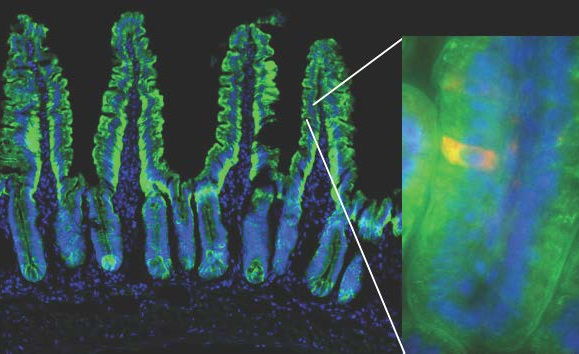

The mouse model used in the study enables the visualization of a dying red cell within the green fluorescently-labeled small intestinal epithelial cells. The green outline of villi shown delineates the single cell layer of the intestinal epithelium. Cell nuclei are shown in blue. Weill Cornell Medicine investigators tracked dying intestinal epithelial cells into the underlying phagocytes (not visible), and asked how their uptake modulates gene expression in those phagocytes.

In their experiments, the scientists expressed a green fluorescent protein fused to the diphtheria toxin receptor within intestinal epithelial cells of mice, which made them visible under a microscope and sensitive to diphtheria toxin. They injected into these mice a carefully titrated dose of toxin into the intestinal walls of mice to induce cell death. Then the team examined the phagocytes that turned green after they internalized dead cells. Macrophages, one kind of phagocyte, expressed genes that help process the increased lipid and cholesterol load they acquired from dying cells. Dendritic cells, another type of phagocyte, activated genes responsible for instructing the development of regulatory CD4 T cells, a class of suppressive white blood cells. Notably, both phagocytes expressed a common ‘suppression of inflammation’ gene signature.